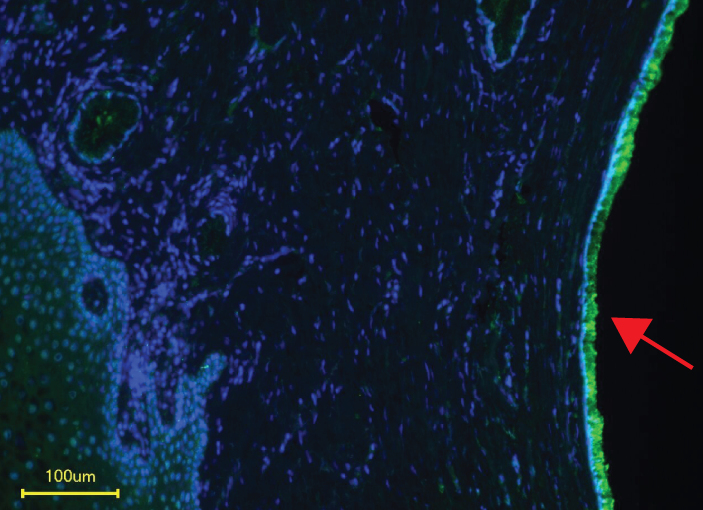

Siglec-11 receptors (red arrow) are expressed on human cervical epithelia, the main infection site of the gonococcus. |

Researchers were surprised to discover, however, that gonococcus doesn’t need its sialic acid coat to bind to Siglecs after all. They learned that the bacterium itself, using a protein called porin (PorB), can also bind multiple human Siglecs on both immune cells and female genital tract cells, including anti-inflammatory Siglec-11 and pro-inflammatory Siglec-16. These findings also suggest that a person’s Siglec variations may influence his or her susceptibility to the infection.